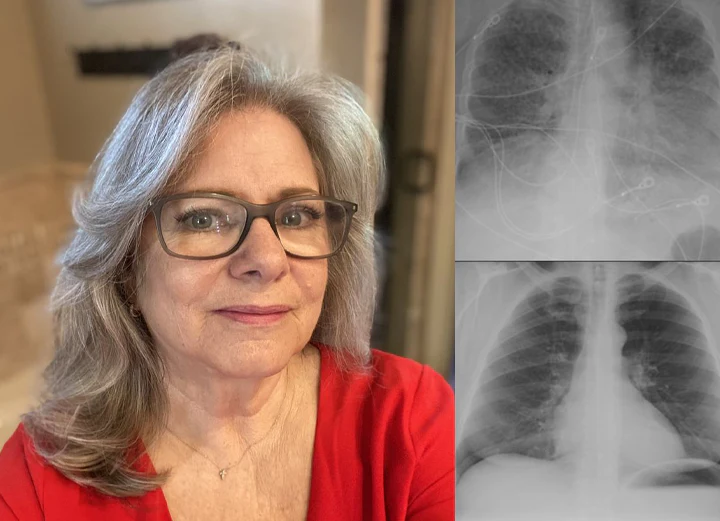

Hear From 150,000+ Satisfied Customers Who Cleared Their Lungs with Timilk® HerbaAir

“Living in a polluted city, I battled constant wheezing and exhaustion for years. Medications helped but made me feel drained. With Timilk® HerbaAir nasal inhalation, I felt my airways open up within 2 minutes of first use! My cough disappeared within two weeks, and breathing became much smoother. The instant relief is incredible.” — Linda M., Age 52,

“After smoking for over a decade, climbing stairs left me breathless. I tried various remedies with no improvement until Timilk® HerbaAir nasal inhalation. I couldn’t believe how quickly I felt relief! After one week, I could walk up five floors without gasping. My constant cough vanished completely.” — Bianca F., Age 47,

“With emphysema for ten years, every morning was a struggle with tight chest and constant mucus. Mullein teas helped a little, but Timilk® HerbaAir nasal inhalation gave me immediate soothing relief from the very first use. Within two weeks, I could walk my dog again without stopping.” — Karen S., Age 68,

Miss Michael Grace

“I used to have chest congestion and difficulty breathing, but after using HerbaAir Mullein Lung Purifier, my chest feels clearer and breathing is much easier. I feel healthier and more comfortable now. I truly recommend it.”

Engr. John Nnamdi - Enugu

“Before using HerbaAir Mullein Lung Purifier, I constantly struggled with chest congestion and shortness of breath. Within a short time, my breathing became clearer and the tightness in my chest disappeared. I feel stronger and healthier now — I highly Impressed.”